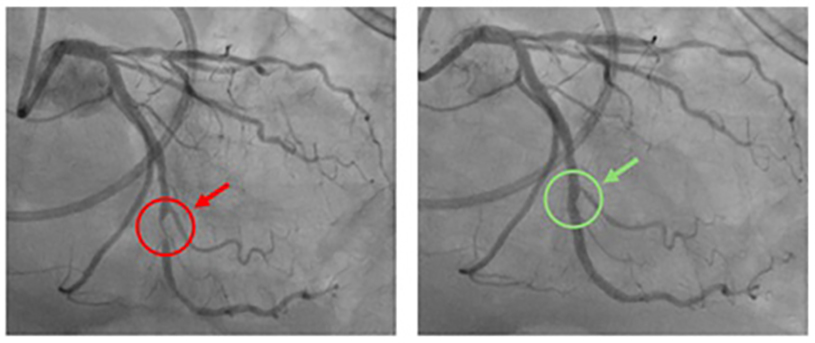

As mentioned above, cardiac catheterization is used to view the arteries of the heart directly. In cases of severe blockage, a stent can be placed to re-open the blood vessel and keep blood flowing to the heart muscle. Below is a picture of a blocked artery (red) that is reopened after stent placement during cardiac catheterization (green).

Case Example: A 60-year-old man who had a history of hypertension and a family history of heart disease. The patient was completely asymptomatic. The primary care physician suggested a calcium CT score and it came back showing moderate risk. After additional testing was performed, a cardiac catheterization was recommended to accurately determine extent of cardiac disease.

The figures above illustrate the coronary angiogram that was obtained during cardiac catheterization. The figure on the left shows a significant blockage of one of the vessels (red circle/arrow). The figure on the right is the same vessel after coronary stenting (green circle/arrow)